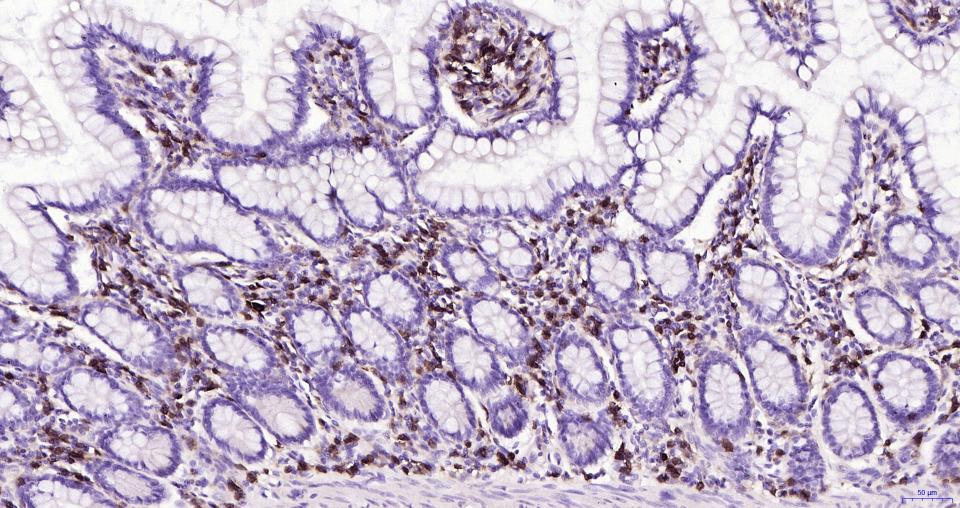

| IHC-P | Human | 1:100-500 | |

| IHC-F | Human | 1:100-500 | |